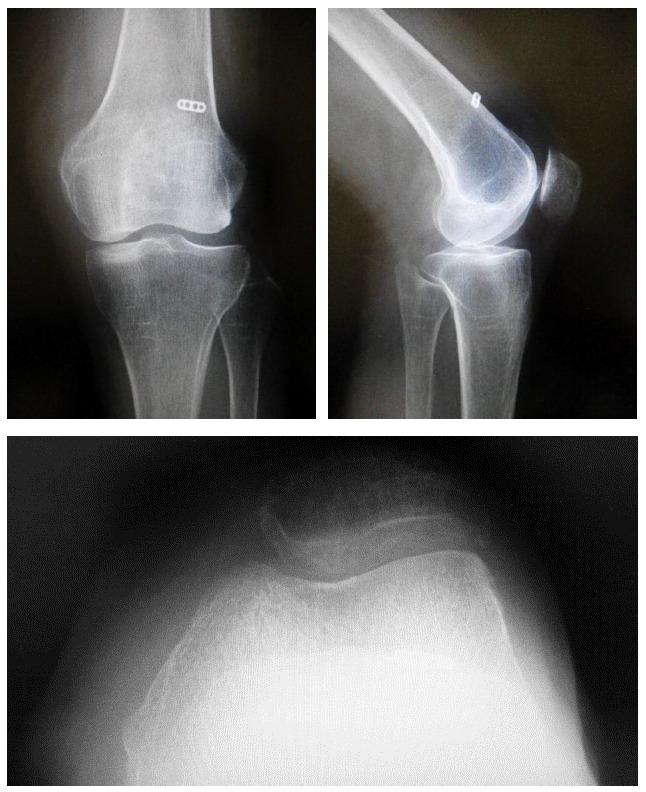

81-year-old female presented with left knee pain, giving way, and patellar instability while climbing stairs, which continued for 18 months. Patellar apprehension test was positive, and roentgenogram showed lateral patellar subluxation. Conservative therapy was not successful; hence, we performed a lateral release and MPFL reconstruction surgery.

一名81岁女性,出现左膝疼痛、打软腿及上楼梯时髌骨不稳定症状,持续18个月。髌骨恐惧试验阳性,X线片显示髌骨外侧半脱位。保守治疗无效,因此我们进行了外侧松解和MPFL重建手术。